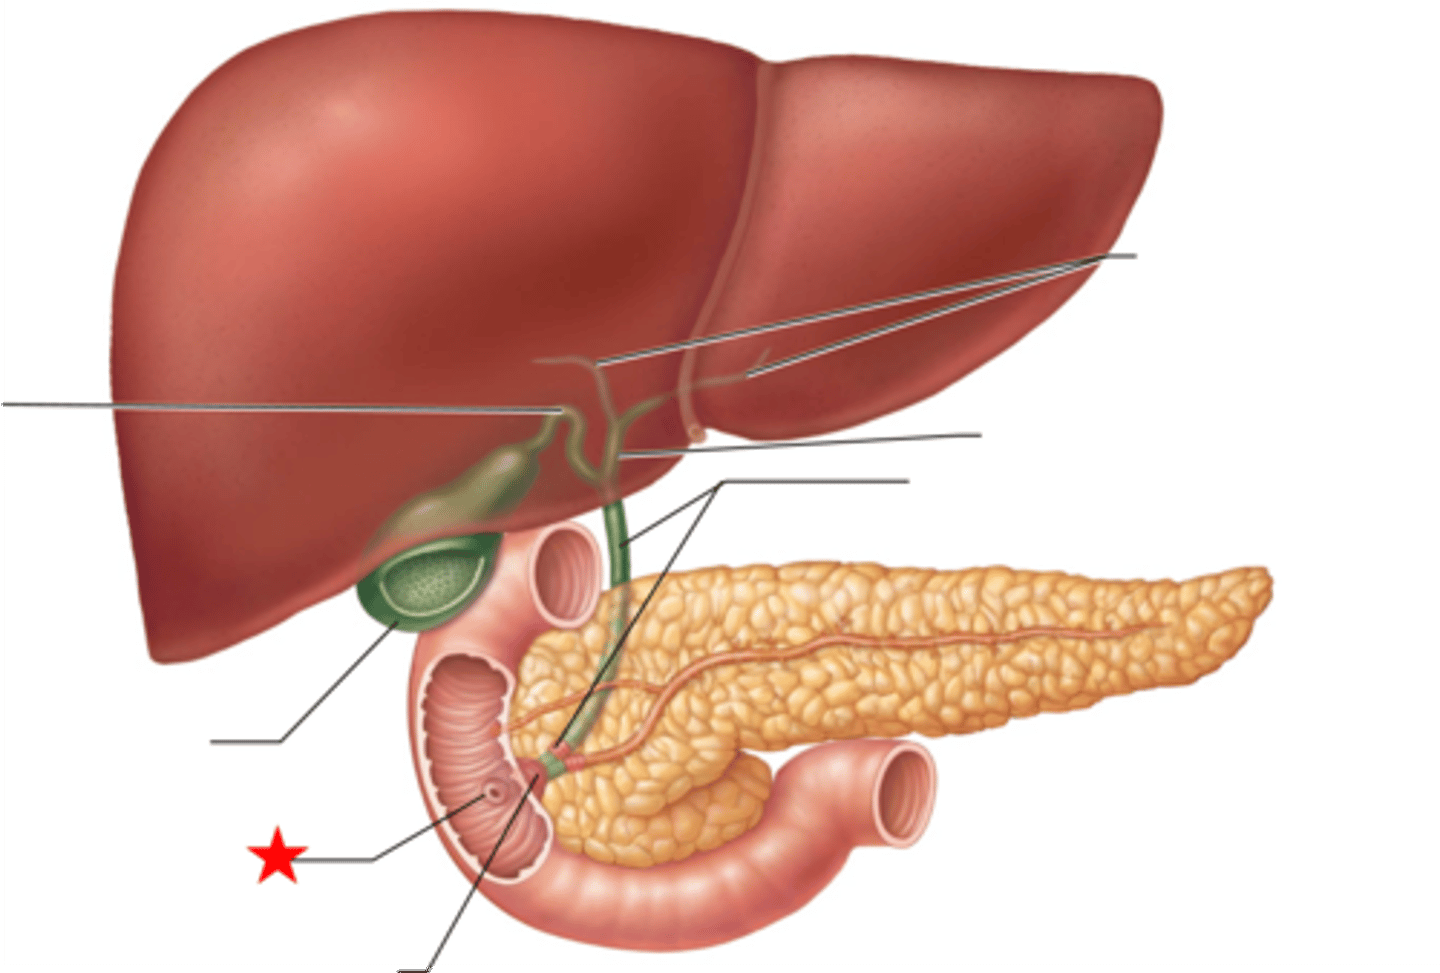

duodenum

A

major duodenal papilla

exit of hepatopancreatic duct

minor duodenal papilla

- #1

- exit for accessory pancreatic duct